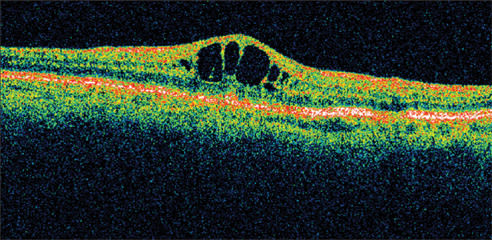

A 71-year-old man who had cataract surgery 3 months earlier was a known steroid responder with elevated IOP following surgery. At presentation, his visual acuity was 20/63. He had a fine epiretinal membrane and CME OD. Retinal thickness was 501 μm on OCT (Figure 4).

Figure 4. A 71-year-old man, who had cataract surgery 3 months earlier, presented with visual acuity of 20/63. He had a fine epiretinal membrane and CME OD. Retinal thickness was 501 μm on OCT.

Figure 5. One month following treatment with nepafenac, vision improved to 20/32 with a marked reduction in retinal thickness. By 12 weeks, visual acuity was still 20/32 with a retinal thickness of 261 μm and an improvement in the appearance of the fovea.

He was treated with nepafenac qid for 6 weeks and tapered over the ensuing 6 weeks. His vision improved to 20/32 by 1 month, with a marked reduction in retinal thickness. By 12 weeks, his visual acuity was still 20/32 with retinal thickness of 261 μm and an improvement in the appearance of the fovea (Figure 5).